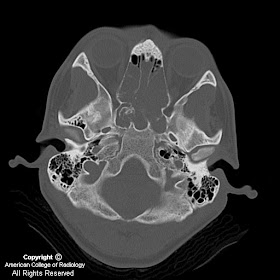

Figure 5 and Figure 6: Axial and coronal CT demonstrate the calcified matrix within the mass taking characteristic “ring and arc” shapes. The anterior and superior walls of the sphenoid sinus are eroded confirming the aggressiveness of the tumor.

Intracranial chondrosarcomas have been shown to be minimally sensitive to conventional radiation therapy, thus requiring radical excision of the tumor for effective management. Therefore, diagnostic imaging with MRI and CT is significant for neurosurgical assessment of tumor invasion and its anatomic orientation with any surrounding vascular, bony, and neural structures. Radiological imaging has enhanced diagnosis as CT is useful in finely delineating tumor invasion, bony invasion, and abnormal “ring and arc” or stippled calcification typical of chondrosarcomas. The tumor is normally isoattenuated or hyperattenuated with some degree of heterogeneous enhancement. MRI with gadolinium allows for evaluation of significant vessels and nerves such as the carotid arteries and optic nerves that lie in the preferred area of tumor growth. Furthermore, the tumor appears with decreased signal on T1 weighted images and increased signal on T2-weighted images. MRI enhancement will be mild to moderate, typically described with a “honey-combing” appearance due to islands of cartilage. In addition, it has been demonstrated that there is only mild edema surrounding chondrosarcomas in contrast to other skull base malignancies. MRI perfusion has also been documented to be effective in differentiating chondrosarcomas from other anterior skull base malignancies by assessing the cerebral blood volume and perfusion. Tumor vascularity is variable depending on the histological type; however, conventional and mesenchymal chondrosarcomas are commonly hypovascular, which differentiates it from the significantly vascular meningioma and metastatic lesion.